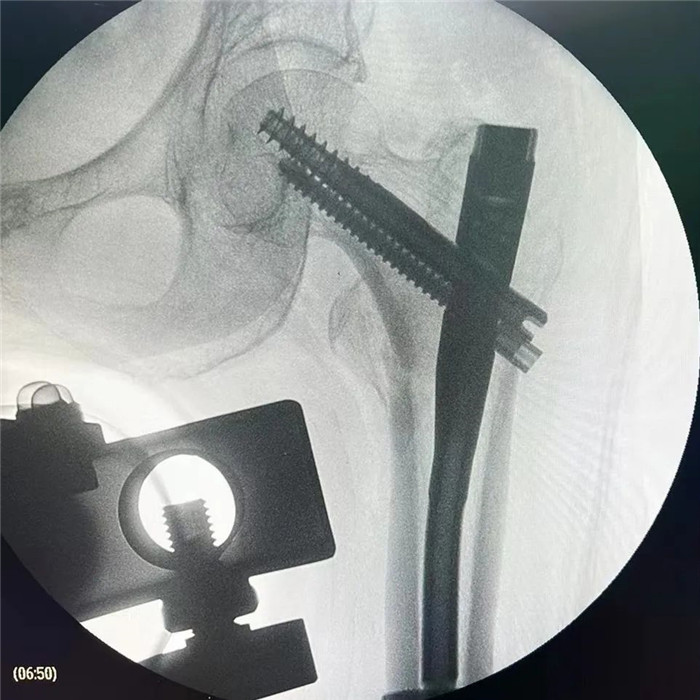

在手术团队及患者家属的大力支持下,罗军主任团队为洪阿婆实施了闭合复位INTERTAN内固定术。虽然手术风险较大,但凭借精湛的技术及丰富的临床经验,手术十分成功而且仅仅用了1个小时,术中出血不多,术后患者恢复得很好,第二天就可以在起床活动,极大的提高了患者的生活质量,避免了长期卧床造成的并发症。